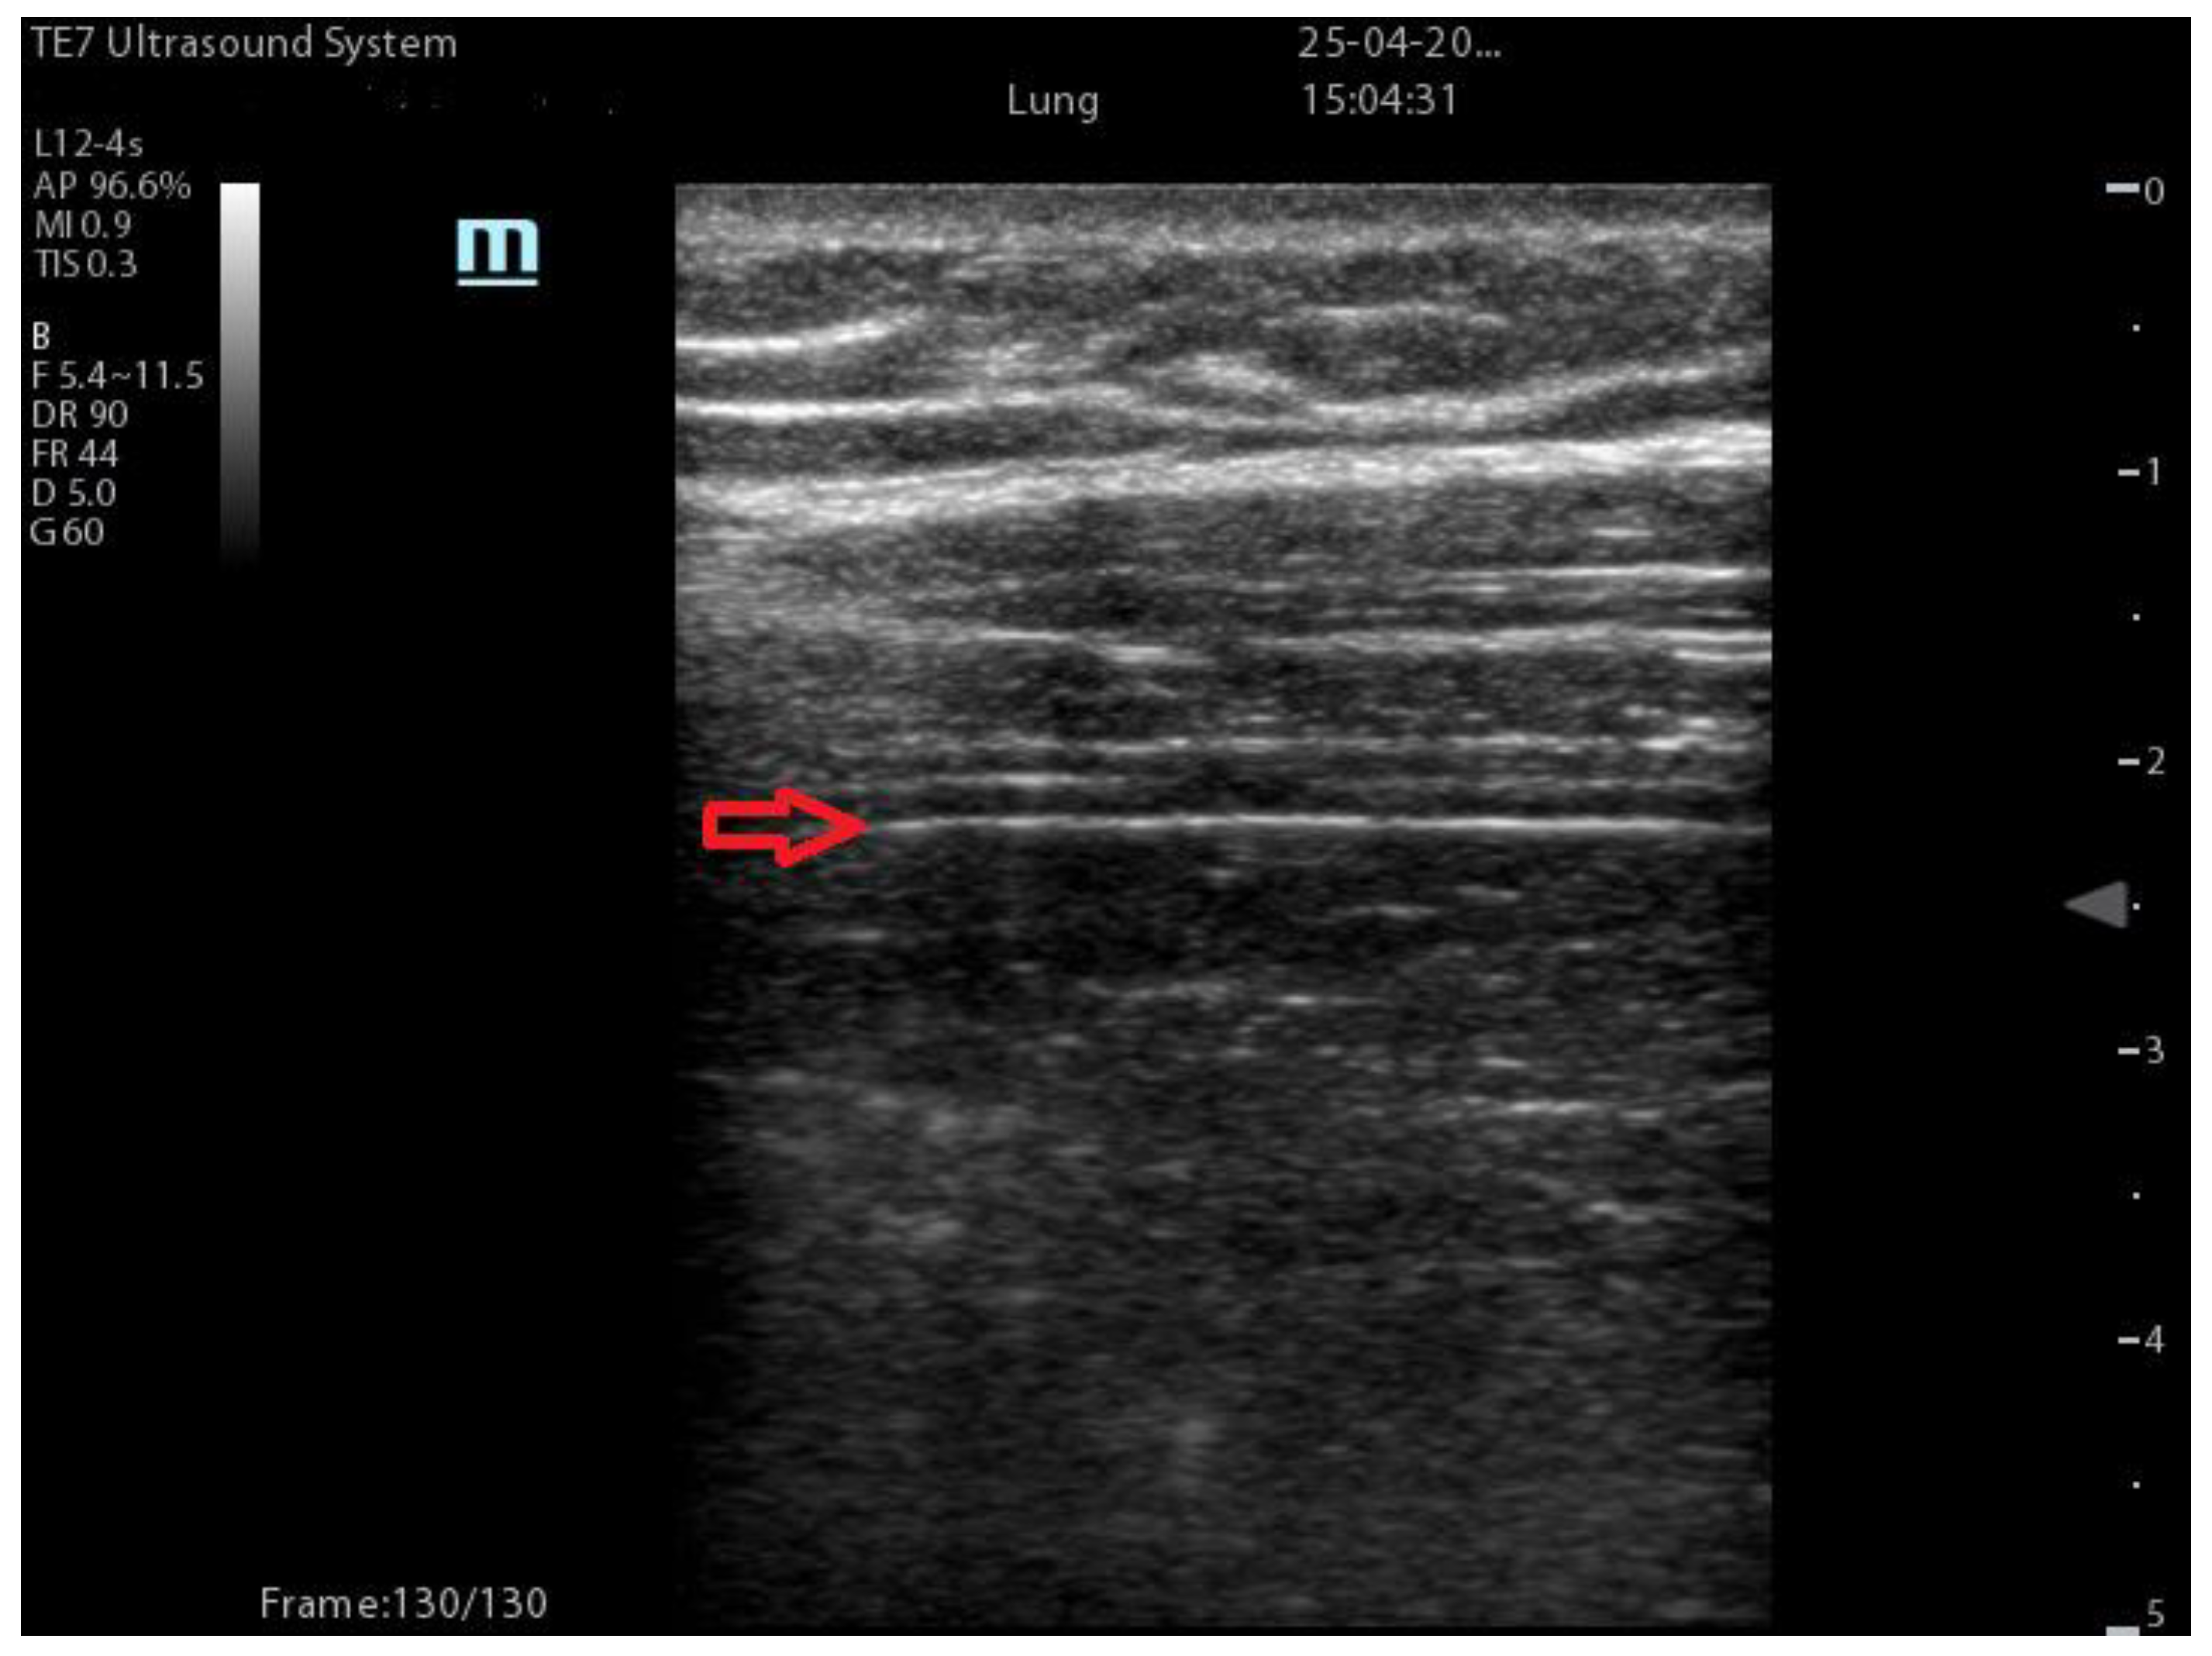

| Coalescent Lung score c-LUS [10,11] | Score 0: presence of A-lines, maximum 2 B-lines Score 1: ≥3 well-spaced B-lines Score 2: coalescent B-lines Score 3: tissue-like pattern | ![]() 12 AREAS |

| Quantitative LUSS (q-LUS) [12] | Score 0: A-lines, maximum 2 B-lines Score 1: artefacts occupying ≤ 50% of pleura Score 2: artefacts occupying > 50% of pleura Score 3: tissue-like pattern | ![]() 12 AREAS |

| Casella score [42] | 0: regular pleural line, presence of horizontal artefacts (A-lines); 1: at least 3 B-lines in at least one scan of the region; the B-lines do not merge one in the other. Small subpleural consolidations ≤1 cm diameter may be present; 2: multiple, converging B-lines, usually determining a so-called “white lung”. Small subpleural consolidations ≤1 cm diameter may be present; 3: presence of at least one consolidation with major axis >1 cm. | ![]() 11 AREAS |

| Dargent score [46] | 0 = normal findings 1 = well-defined B-lines 2 = coalescent B-lines 3 = consolidations | ![]() 12 AREAS |

| Modified LUS score [47] | 0: well-spaced B-lines <3 1: well-spaced B-lines ≥3 2: multiple coalescent B-lines 3: lung consolidation Plus, plural line is quantitatively ranked as follows: 0: normal 1: irregular pleural line 2: blurred pleural line | ![]() 12 AREAS |